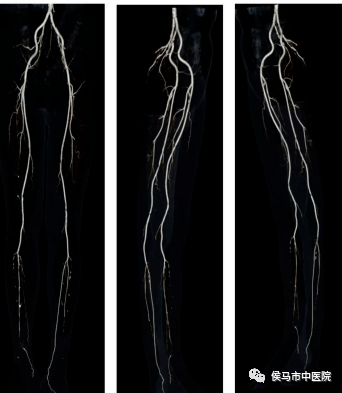

5、双下肢动脉CTA

通过CTA可以明确下肢动脉形态、有无管腔狭窄、有无闭塞、动脉硬化程度、有无动脉瘤样扩张等情况。是检查下肢动脉疾病的一项重要无创检查手段。